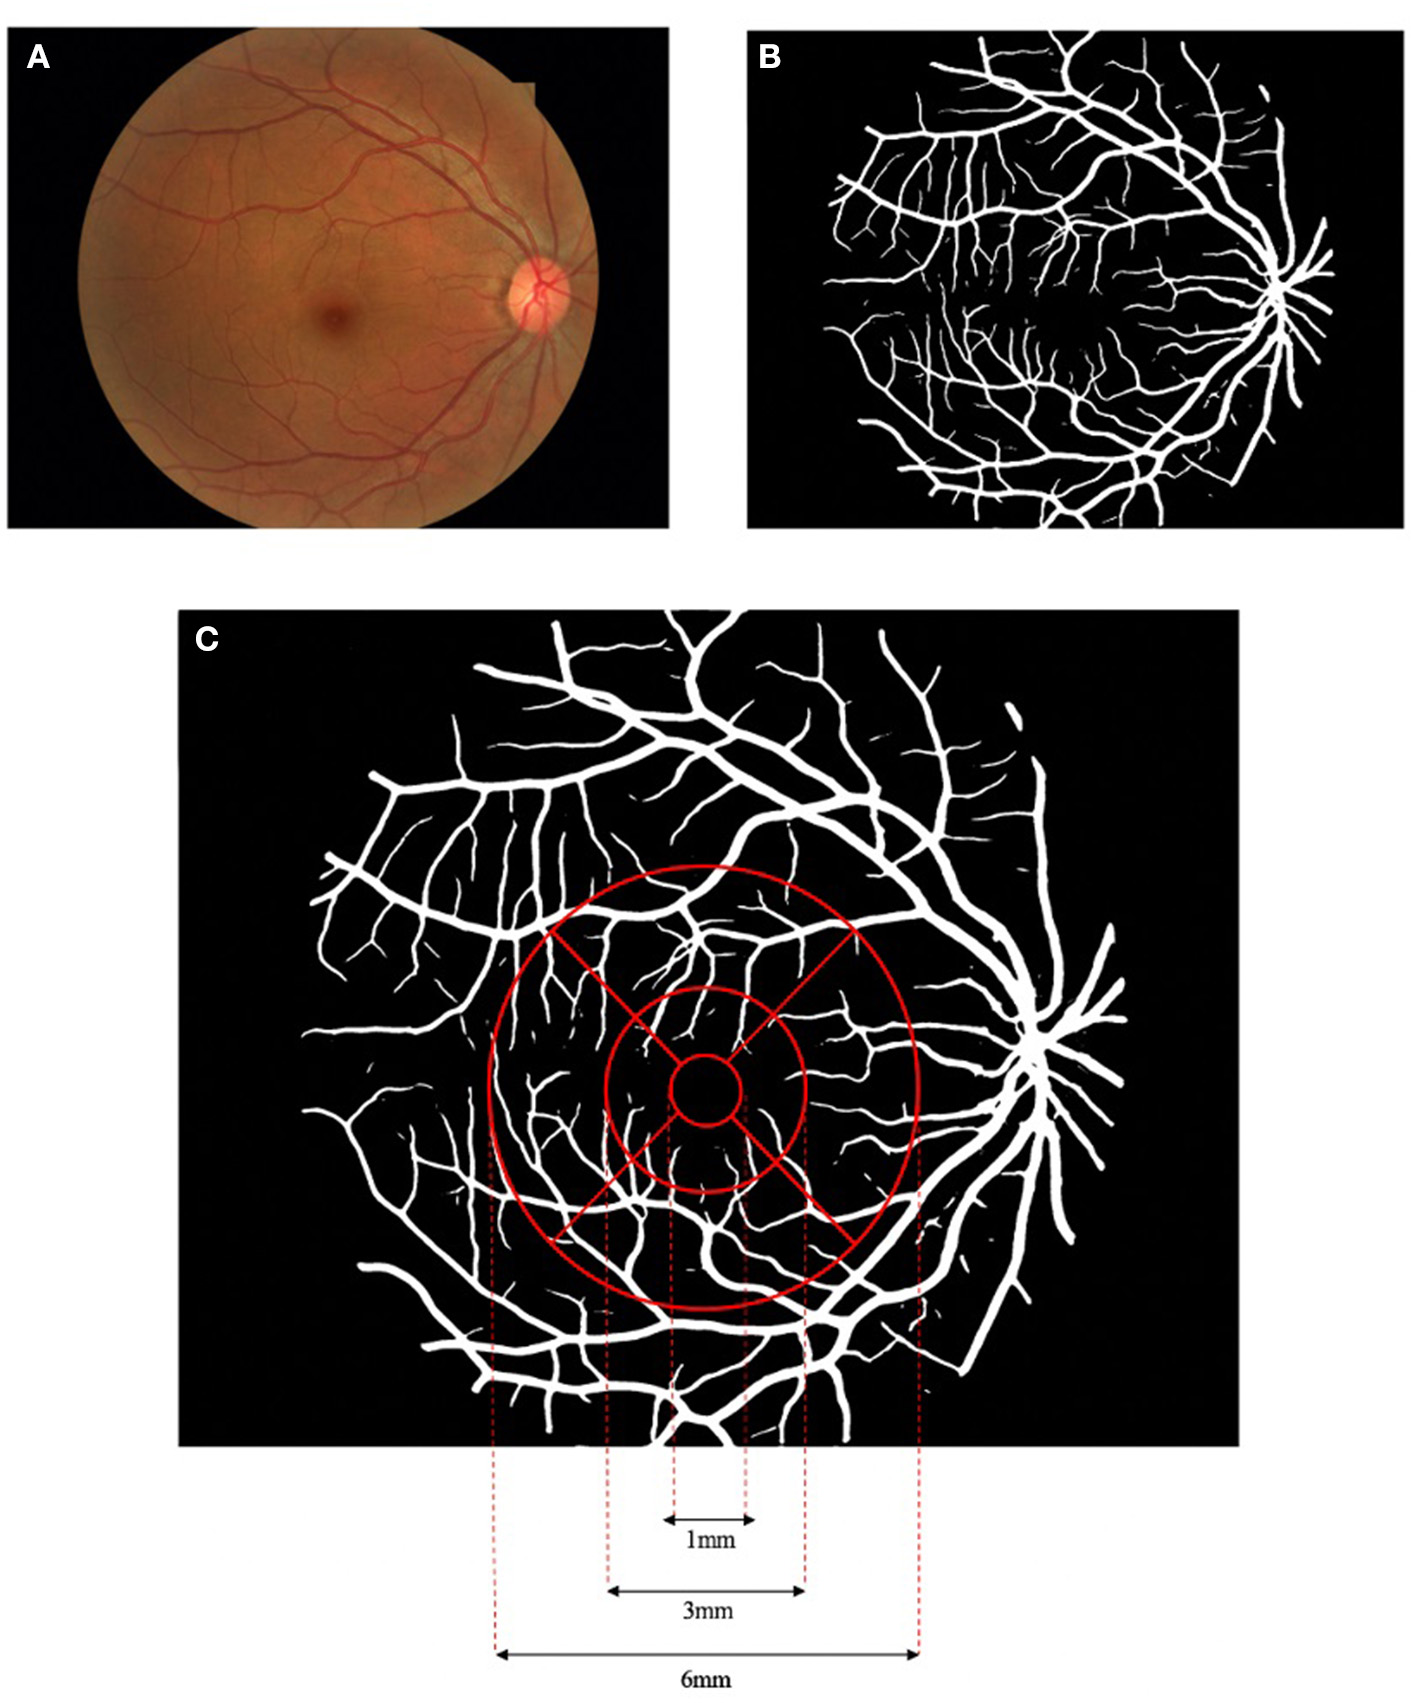

With the color fundus photographs acquired from all the enrolled subjects, multiparametric measurements of the macular vascular geometry were performed with our self-developed fundus photography analysis software. Details of the method could refer to former publications (31). In brief, the fundus image (Figure 1A) is first processed by adaptive histogram equalization and bilateral filtering to enhance the contrast between the blood vessels and the background. The enhanced image is then input into a D-GAN-based retinal vascular segmentation algorithm, exporting a binarized retinal vascular network map (Figure 1B). The introduction of the dense blocks into the GAN enables more efficient processing between separated spatial regions of fundus images, building a more powerful generator to segment smooth, clear, and detailed blood vessels. The segmented vessel network binary image is then further analyzed by our software to quantify the macular vascular geometry based on Early Treatment Diabetic Retinopathy Study (ETDRS), separating the macular area into nine sectors (Figure 1C). The diameter of the concentric circles centered at the fovea centers are 1, 3, and 6 mm, respectively, with the inner and outer rings both evenly split into four parts (superior, inferior, nasal, and temporal). Since the innermost circle around the fovea avascular zone seldom has vessels in fundus photographs, this area is excluded for further data analysis. Vascular geometric parameters including fractal dimension (Df), vessel area rate (VAR), average vessel diameter (Dm), and vessel tortuosity (τn) were calculated for both the inner and outer ring as well as their sub-sectors. Note that, Df is a statistic value calculated with vessel skeletons that describes the space-filling degree of a fractal, measuring the spatial availability of a complex shape, which to some extent can reflect the density and complexity of the selected microvascular network (34–36). VAR is the ratio of the vascular area to the total area of the selected region, which could comprehensively reflect vascular density while Dm is the mean vessel diameter of the vessels in the region. τn is defined by multiple subdivision-based algorithms calculating the maximum of the accumulated absolute tangent angle difference of the sub-segments of the blood vessels multiplied by a transformed sigmoid learning curve function of the inflection point numbers of the vessel segment curvature sign, emphasizing the human tortuosity assessment nature focusing not only global but also on local vascular features (31).

Figure 1

Flowchart of the macular vascular geometry assessment according to Early Treatment Diabetic Retinopathy Study (ETDRS). The fundus photograph (A) was pre-processed and input to the dense block generative adversarial network (D-GAN) segmentation system, exporting a binarized retinal vascular network map (B), and further analyzed to quantify the macular vascular geometry based on ETDRS (C).